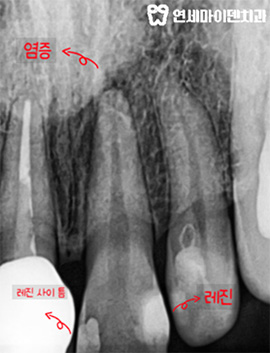

신경치료도 했던 치아인데,, 앞니 통증과 뿌리 염증이 지속되었습니다.

연세마이덴치과는 당시 임시치아로만 마무리된 상태였는데 통증도 있어서

다시 한 번 내부를 들여다 보았습니다.

깨끗하게 내부 치료를 다시 하고 재감염이 없도록 레진코어까지 제대로 마무리했습니다.